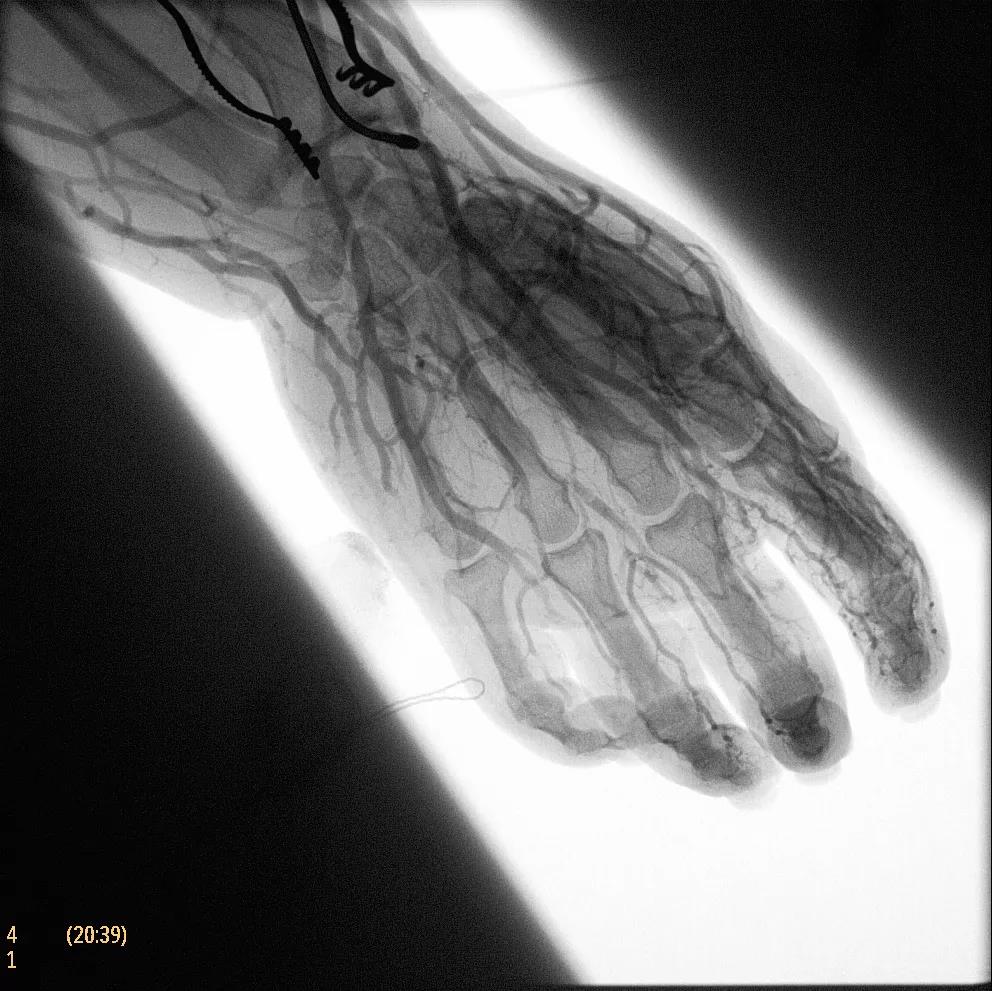

( Zenition 70采用與Azurion平臺相同的圖像處理算法。

為了獲得清晰的高質(zhì)量圖像,Zenition 70 采用了與公司Azurion平臺相同的圖像處理算法,可提供患者解剖結(jié)構(gòu)的高清可視化和更大的可視區(qū)域。飛利浦的MetalSmart軟件等功能可確保圖像質(zhì)量,該軟件可自動調(diào)整圖像的對比度和亮度,以便在視野中存在金屬物體(如植入物)時提高圖像質(zhì)量 - 這一特性使Zenition 70在整形外科中特別有用。